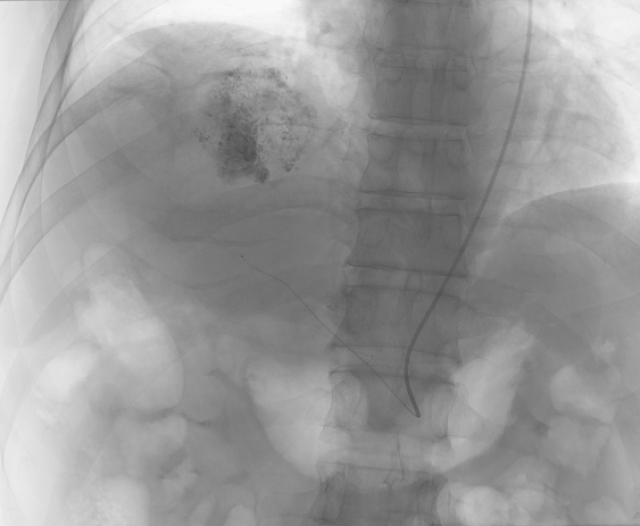

经左侧桡动脉入路TACE术中透视图

“手术入路的选择需结合患者的具体情况进行临床选择。”张琳说。此次经左侧桡动脉入路的患者,2年多前被发现患有右肝多发肿瘤,在外院曾接受过多次介入、射频、靶向及免疫等综合治疗,入院后经综合评估已经达到TACE治疗的条件,但由于患者右侧腹股沟反复多次手术,皮肤与皮下组织存在瘢痕,再次经右股动脉入路,出现血管并发症风险较高。在评估后,张琳为其制订了行左侧桡动脉入路的TACE治疗,术前在心内科主任医师缪国斌的指导下,通过左手艾伦(ALLEN)试验,确认左手桡动脉与尺动脉供血情况满足手术条件。术后,患者左手的活动、感觉等都没有出现不适,复查血常规、肝肾功能等结果均为正常,术后2天出院。